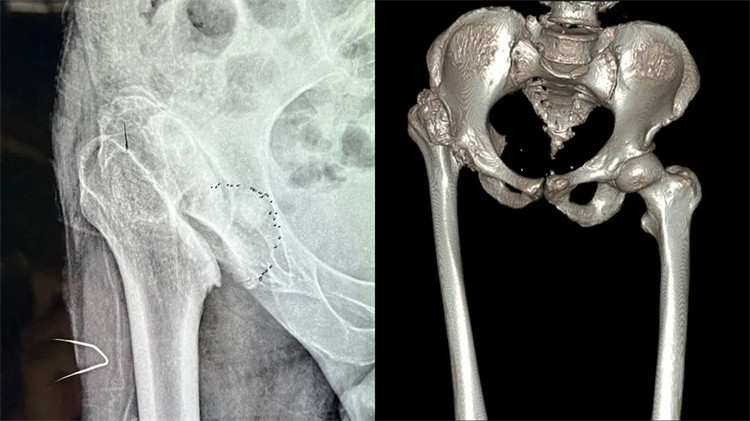

患者術(shù)前嚴(yán)重變形的髖關(guān)節(jié)

周大伯來院后經(jīng)X線片及CT檢查,發(fā)現(xiàn)右側(cè)股骨頭壞死、形態(tài)失常,已經(jīng)完全脫離正常的位置,且很難找到真臼,右側(cè)髖臼形態(tài)失常、部分骨質(zhì)缺失。想要徹底解決周大伯的問題,需要進行右側(cè)人工全髖關(guān)節(jié)置換。但周大伯患病50余年,且有過失敗的手術(shù)病史,髖關(guān)節(jié)感染后遺癥,髖關(guān)節(jié)脫位,長短腿5公分,手術(shù)難度系數(shù)較大,不能有任何偏差,稍有偏差,嚴(yán)重者可影響手術(shù)效果,留下后遺癥。